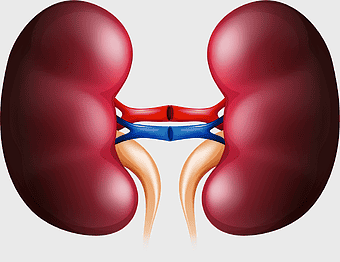

kidney anatomy, human kidney illustration, kidney cancer awareness, kidney organ diagram, renal system structure, medical kidney image, urinary system components -

kidney anatomy diagram, human kidney structure, retroperitoneal space illustration, blood vessels in kidneys, renal system visualization, medical kidney illustration, kidney cross-section analysis -